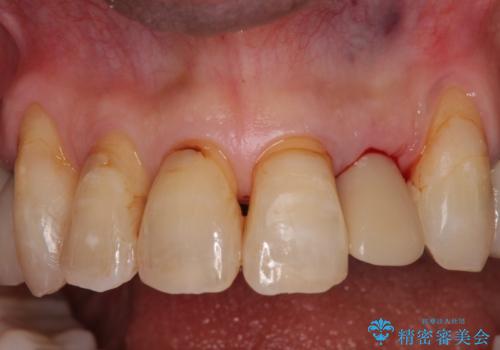

- 前歯のセラミッククランが外れてしまったとのことで来院された患者様です。

診察をしたところ、歯根に縦破折が認められ、抜歯が必要と判断されました。

抜歯、インプラント埋入、仮歯の装着が同時に可能な1DAYインプラントが適用可能と判断されたため、インプラントによる補綴治療を行うこととしました。